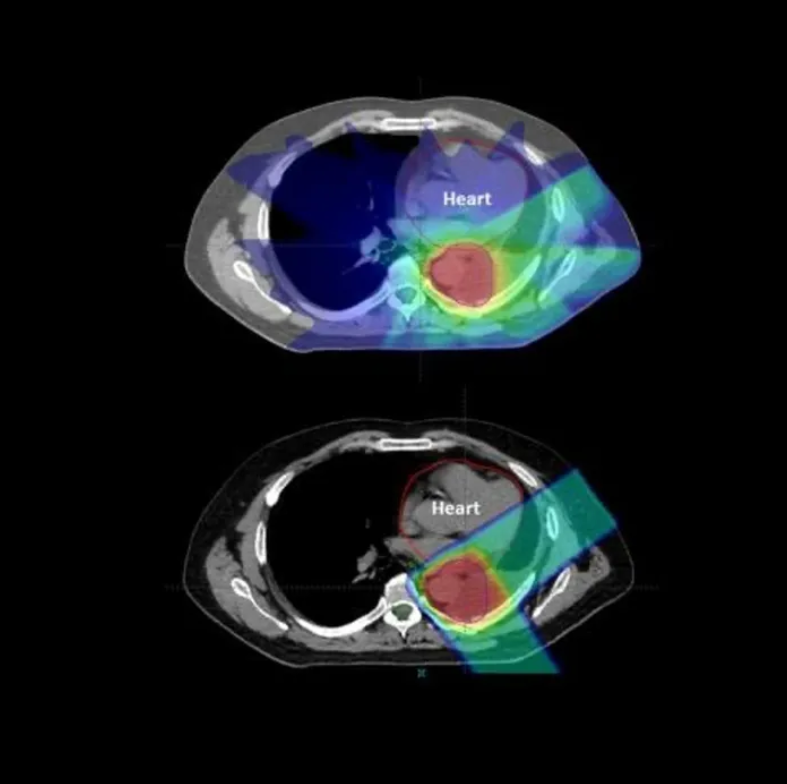

Dr James Wilson is a London-based private oncologist with expertise in lung cancer, skin cancer, and advanced radiotherapy for Stage 4 cancers. He offers rapid access to chemotherapy, immunotherapy, targeted therapy, and precision radiotherapy - including proton beam therapy. Known for clear communication and personalised care, Dr Wilson helps patients take control with expert second opinions and tailored treatment plans. Appointments are often available within days, either in person or via video. Video consultations are often possible on the same or next day. Trusted by patients Specialist in complex and advanced cases Precision-led, consultant-delivered care